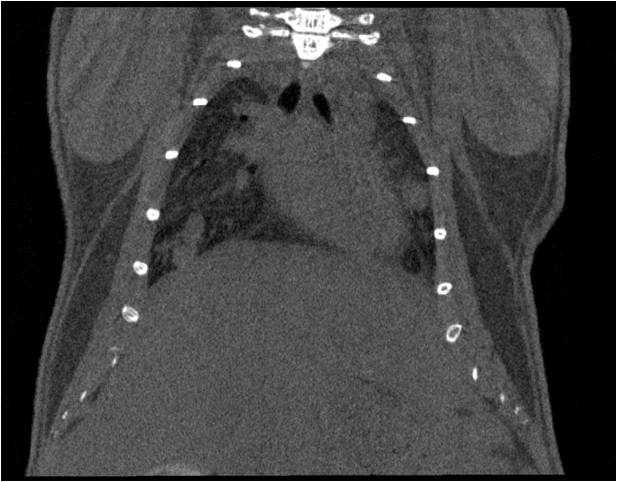

肺轉移

小鼠模式,22.5μm像素

正常

正常.jpg

8天                                                                  14天

8天.jpg  14天.jpg